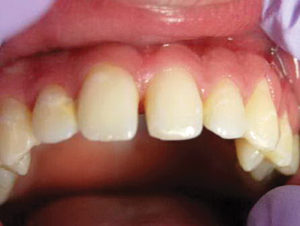

Este adolescente de 16 años tuvo una recaída post-ortodoncia de un diastema de la línea media y era consciente del espacio. Se dieron opciones para cerrar el espacio, incluyendo seis meses de corrección de ortodoncia versus corrección restaurativa con restauraciones directas. Debido a la forma larga y delgada de sus incisivos centrales, el paciente, su madre y yo acordamos que la mejor opción sería la corrección restauradora.

Figura 1. Foto preoperatoria de un diastema de 2.75 mm en un adolescente preocupado (recaída post ortodóntica). |

Figura 2. Después de la colocación de dos matrices Bioclear, los dientes se biselaron ligeramente, se grabaron con ácido y se unieron con Scotchbond Universal. Activa Bioactive Restorative A2 fue colocado y curado. Las restauraciones de los dientes fueron terminadas y pulidas. |

Figura 3. Cuando uso Activa, se notó una naturaleza de mezcla y camaleón del material. Por lo general, combina maravillosamente con el esmalte cuando se coloca como una restauración de un tono en la parte anterior. Se colocó un retenedor fijo 1-1 después de las restauraciones para evitar recaídas adicionales. |